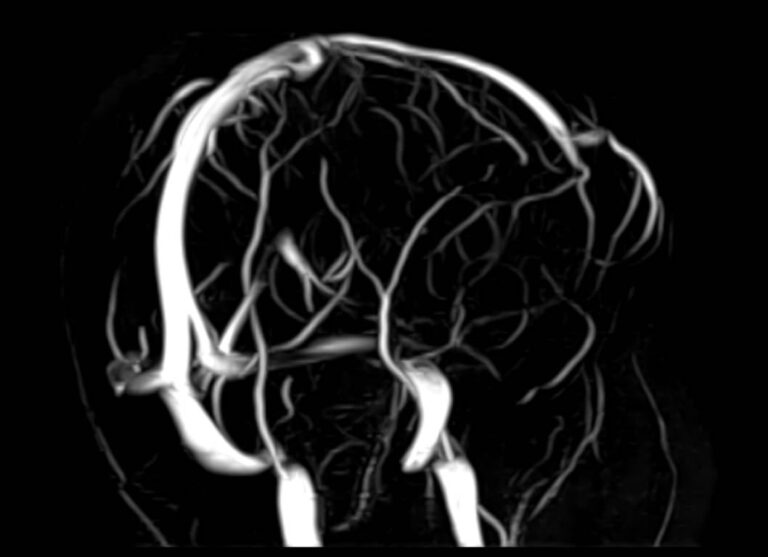

Исследования выполняются на современном высокопольном томографе экспертного класса TOSHIBA VANTAGE TITAN 1,5 Тесла, который использует разные режимы сканирования с толщиной среза от 1мм в различных плоскостях с последующей цифровой обработкой полученных данных для создания трехмерных изображений. МР-ангиография отображает состояние артериальной системы кровоснабжения головного мозга. МР-венография головного мозга позволяет детально изучить особенности венозного русла головного мозга.

Компьютерная программа обрабатывает данные, полученные при сканировании, и формирует объемные изображения как самого мозга, так и сосудистой системы в отдельности без прилегающих тканей. Методики применяются одновременно и взаимодополняют друг друга.

• патология нервов на фоне сосудистых проблем (вазоневральный конфликт — сдавление нерва близлежащим сосудом, также на фоне патологической извитости, аневризмы, сосудистой мальформации).